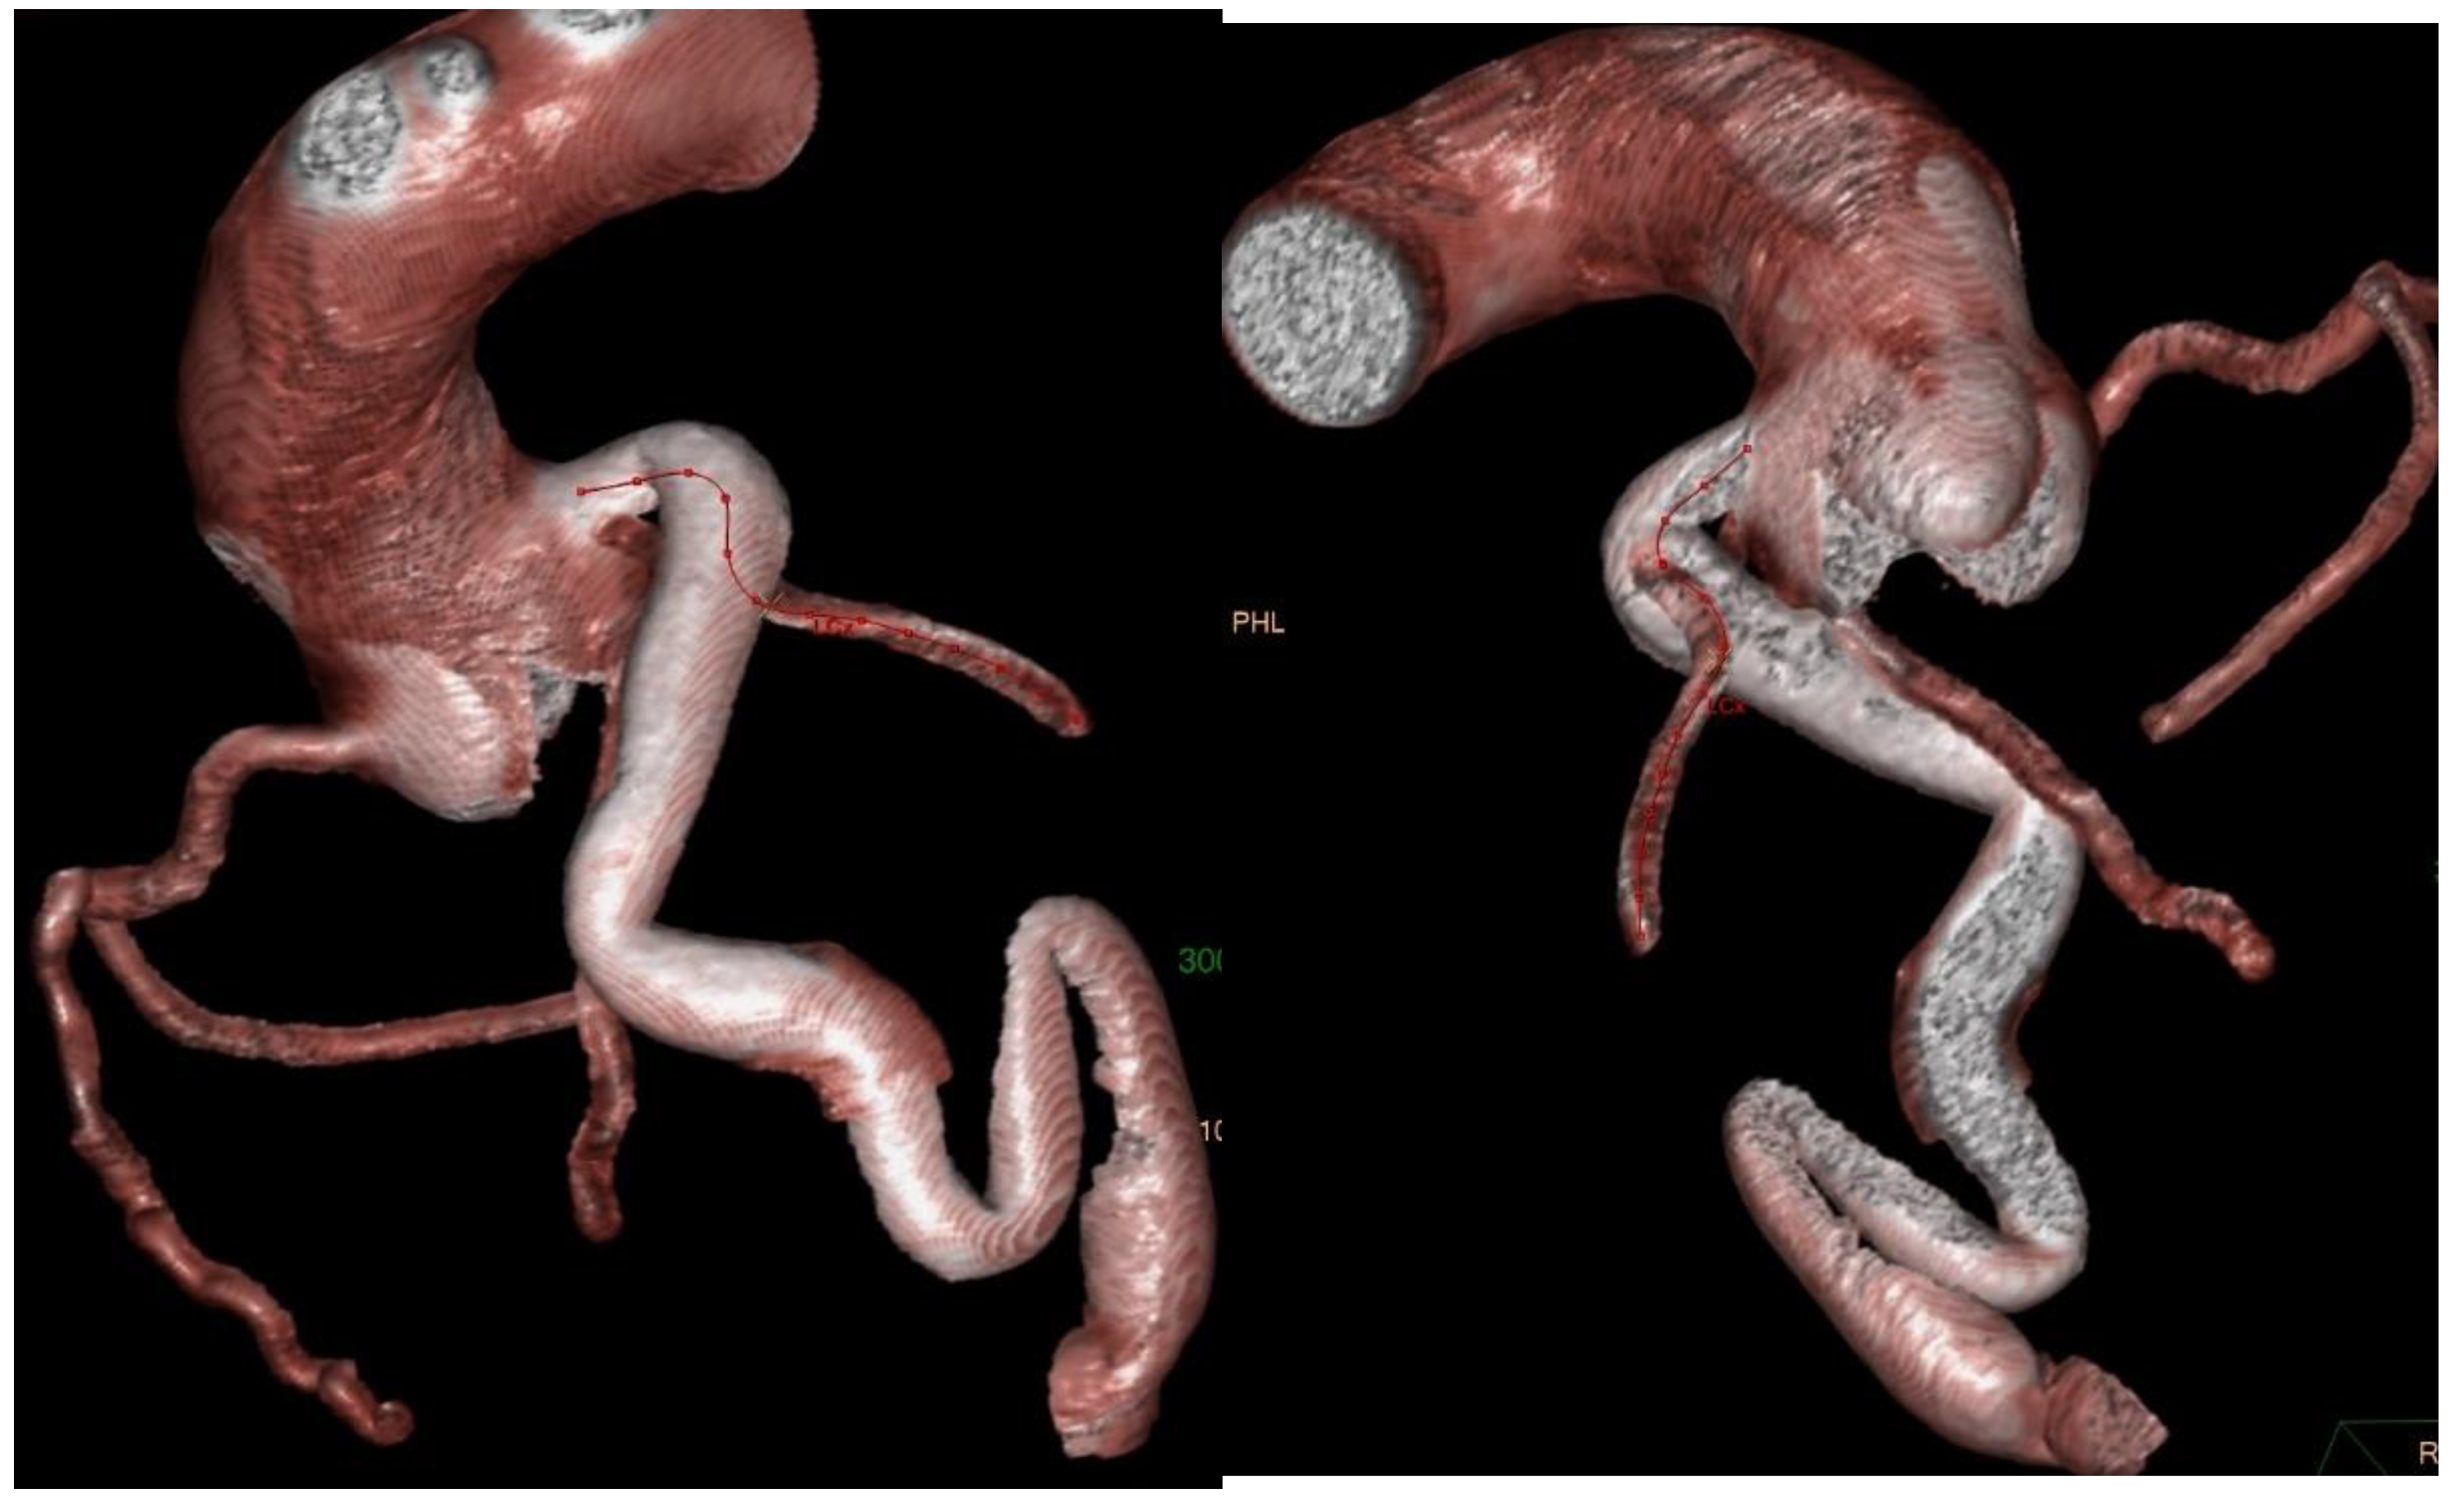

2. Case Presentation